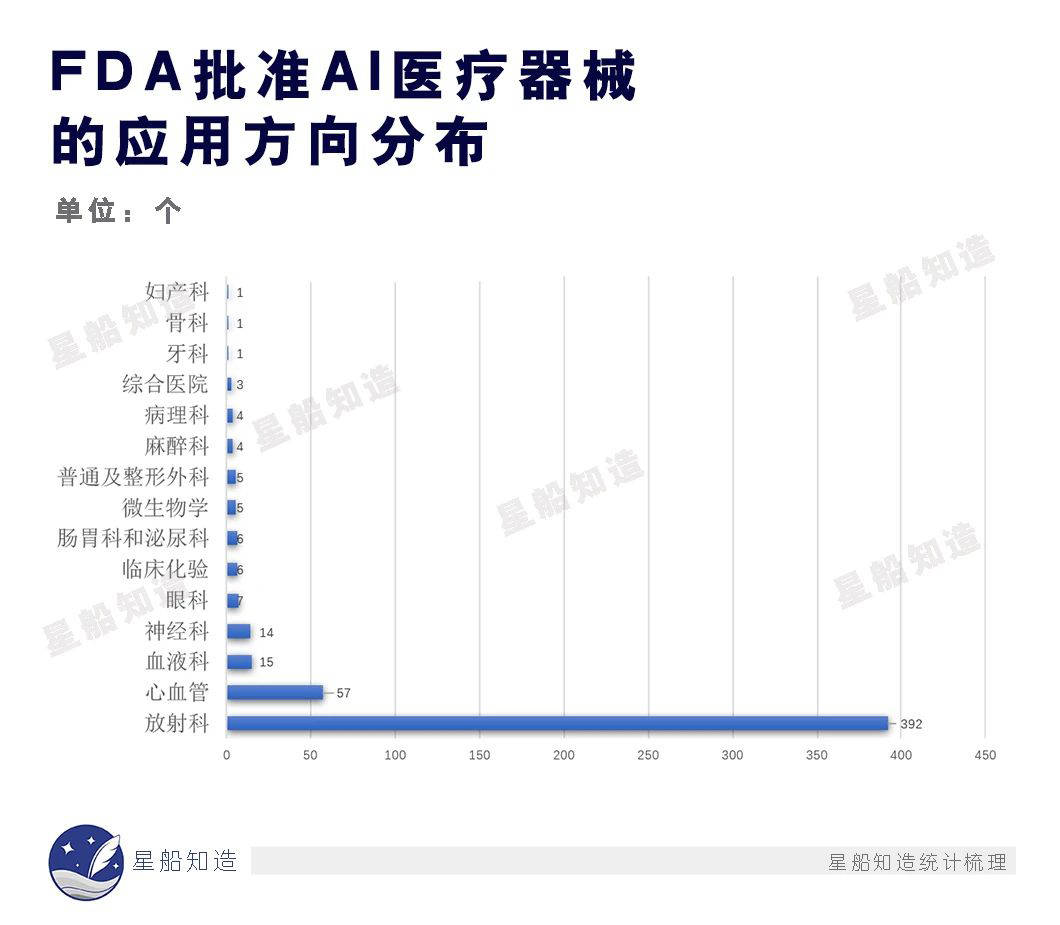

梳理美国FDA(美国食品药品监督管理局)截至2022年底累计批准的521款AI医疗器械,统计其应用科室后可看到,以识图阅片为主要工作的放射科承载了最多的AI器械。

而不论是CT、X射线、磁共振检查,AI产品目前都主要在肺部医学影像中扎堆。